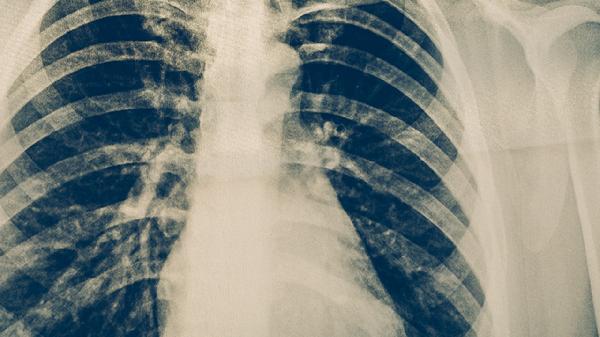

常用药物包括茶碱缓释片改善通气功能,呋塞米片减轻水肿,地高辛片增强心肌收缩力。合并感染时需使用盐酸左氧氟沙星片等抗生素。肺动脉高压患者可能需波生坦片等靶向药物。所有药物均需严格遵医嘱使用,注意监测电解质及药物不良反应。

慢性阻塞性肺疾病患者需规范使用布地奈德福莫特罗粉吸入剂控制气道炎症。睡眠呼吸暂停综合征患者需持续气道正压通气治疗。肺结核活动期需异烟肼片联合利福平胶囊抗结核治疗。有效控制原发病可阻止肺心病进一步恶化。